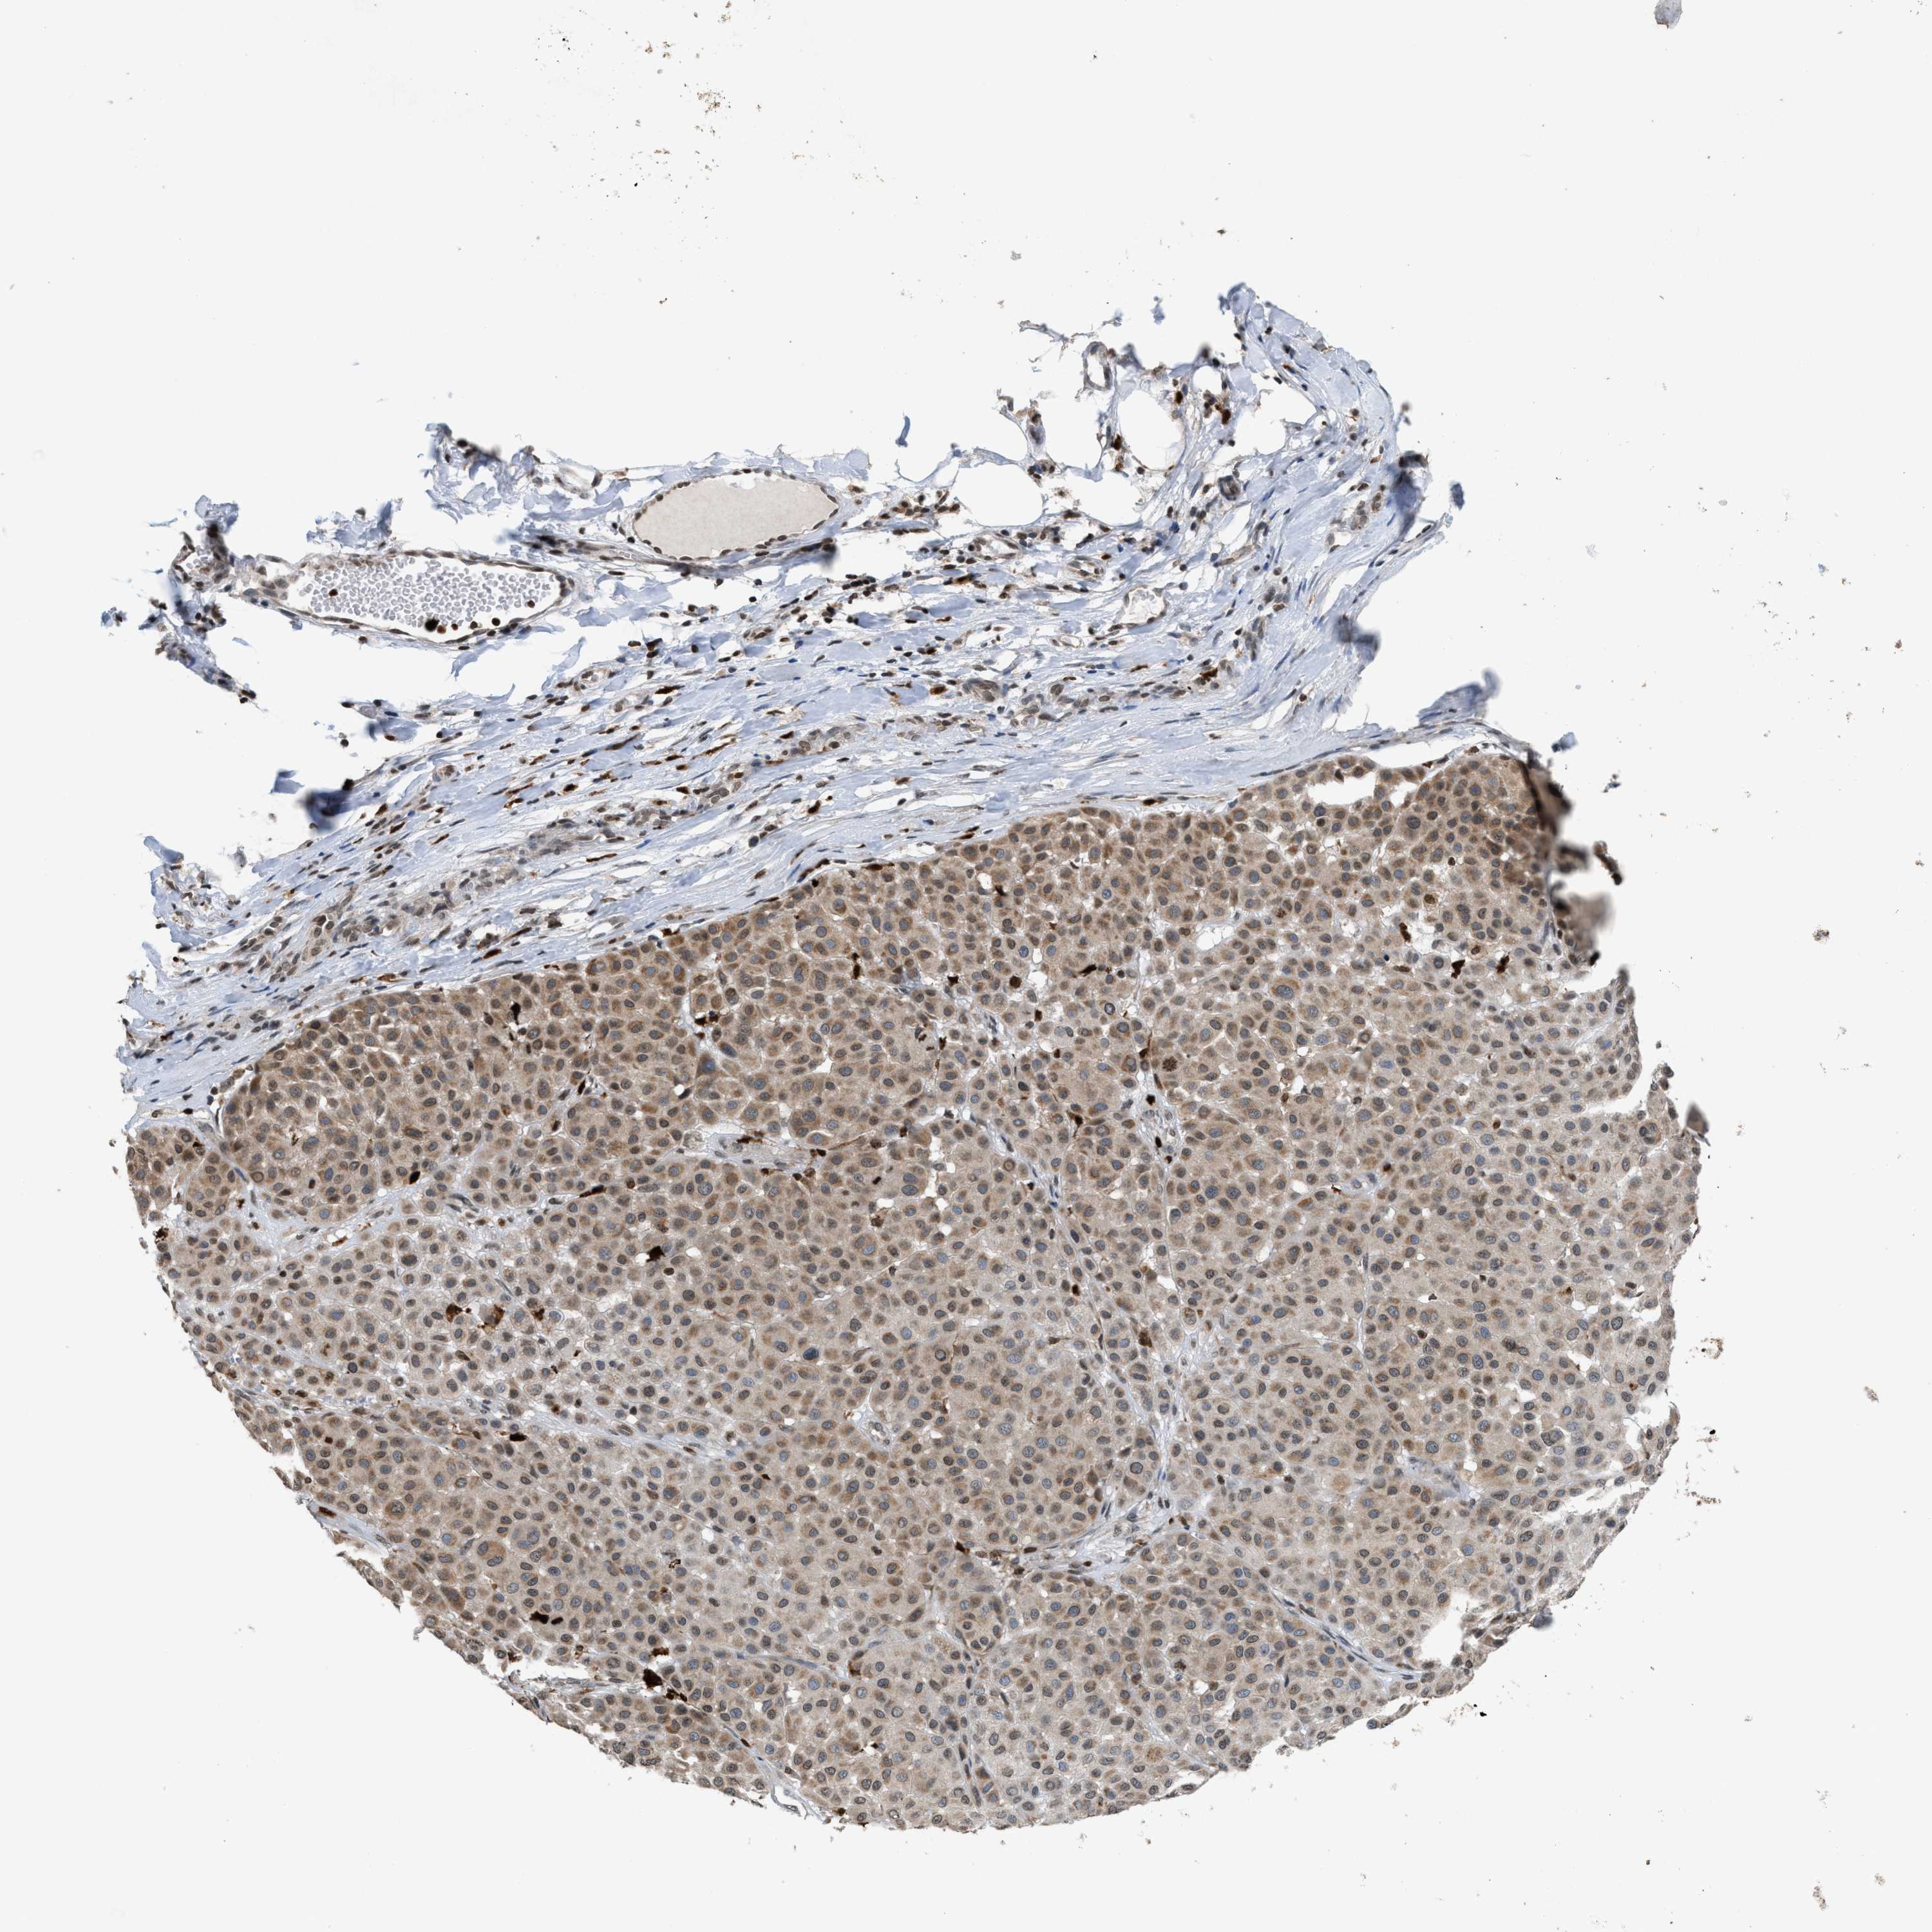

MELANOMA - Protein expressioni

A mouse-over function shows sample information and annotation data. Click on an image to view it in a full screen mode. Samples can be filtered based on level of antibody staining by selecting one or several of the following categories: high, medium, low and not detected. The assay and annotation is described here.

Note that samples used for immunohistochemistry by the Human Protein Atlas do not correspond to samples in the TCGA dataset.

Antibody stainingi

Antibody staining in the annotated cell types in the current human tissue is reported as not detected, low, medium, or high, based on conventional immunohistochemistry profiling in selected tissues. This score is based on the combination of the staining intensity and fraction of stained cells.

Each image is clickable and will lead to virtual microscopy that enables deeper exploration of all samples and also displays staining intensity scores, fraction scores and subcellular localization as well as patient and tissue information for each sample.

Antibody HPA022470

Antibody HPA031079

Staining

High

Medium

Low

Not detected

Intensity

Strong

Moderate

Weak

Negative

Quantity

>75%

75%-25%

<25%

None

Location

Nuclear

Cytoplasmic/membranous

Cytoplasmic/membranous,nuclear

Malignant melanoma, NOS

Malignant melanoma, Metastatic site